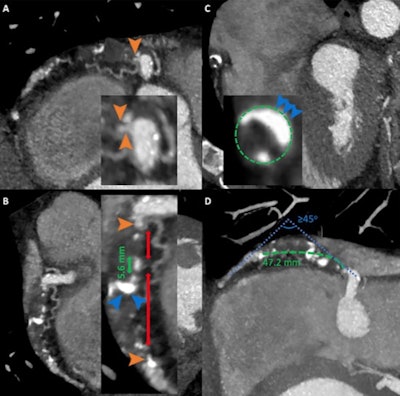

- CCTA could be used to craft an "anatomy roadmap" for physicians performing interventional procedures. "The ability of CCTA to accurately measure lesion length may be employed in prior planning for percutaneous coronary interventions, as it allows a complete visualization of coronary vasculature without foreshortening and overlapping, which is frequently encountered with invasive angiography," the group wrote.

- CCTA could be used to quantify and characterize heart plaque. "The ability of CCTA not only to identify and quantitatively evaluate structure of atherosclerotic plaque but also provide detailed anatomic information of the entire coronary vasculature makes it a powerful diagnostic tool in preprocedural planning and periprocedural guidance of chronic total occlusion percutaneous coronary interventions," the researchers wrote.